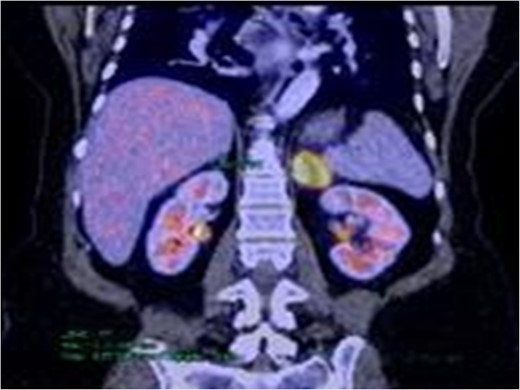

The patient remained asymptomatic during subsequent clinical check-ups. However, in the first CT scan of follow-up 3 months after surgery, a marked increase in the volume of the left adrenal gland was detected. After discussing the case at the multidisciplinary team meeting, a positron emission tomography–CT (PET–CT) scan was performed. A hypermetabolic and expansive lesion was evidenced in the left adrenal gland, of 52 × 32 mm2 in diameter, with a standardized uptake value (SUV) of 13.4, which was interpreted as an adrenal metastasis (Fig. 2). A laparoscopic left adrenalectomy was performed and the patient was discharged 48 h after an uneventful postoperative course. Pathology report was consistent with adrenal metastatic disease from a moderately differentiated adenocarcinoma of colorectal origin (Fig. 3).

PET–CT frontal view. Increased uptake and metabolism (SUV 13.1) to left adrenal level is observed.

Since metastatic adrenal lesions are usually nonfunctional and have few to no symptoms of local invasion, imaging studies are an important tool in the differential diagnosis. Tomographic features of malignant lesions include: size >3 cm, attenuation >10 Hounsfield units, heterogeneity and increased vascularity [7]. Note that the nodule found in the first CT scan of our case, lacked of all the mentioned features. Furthermore, the PET–CT findings are considered positive if the SUV in the adrenal tumor is greater than or equal to the liver. Recently it has been suggested that an SUV of 3.1 is useful in differentiating malignant and benign lesions [8]. In our case, after the resection of the primary tumor, the adrenal lesion showed a SUV of 13.4, reinforcing the oncological origin of this tumor.